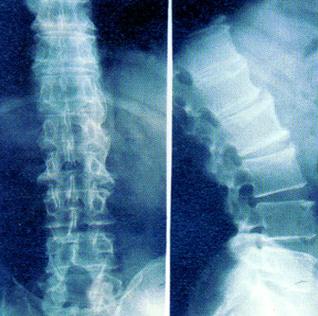

强直性脊柱炎多数情况下是发生在16到25岁的青年人,早期的时候症状表现并不明显,不过有一些病人在早期的时候就有可能出现全身症状。比如有的人早期发病的时候就可以感觉到身体乏力,身体还会逐渐消瘦。

强直可以表现出一些关节病的症状,比如发病之后病人的关节部位会产生炎性疼痛,而且患处的肌肉会有痉挛现象,患者的关节会变得比较僵硬,特别是在早上的时候关节僵硬的感觉特别明显。

有一部分强直病人可能出现前胸疼痛或者是背部疼痛的现象,甚至容易出现驼背畸形,这很有可能是因为强直性脊柱炎与胸椎病变同时发生而引起的。